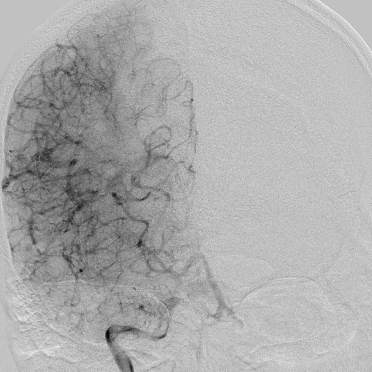

相逢就是缘,有求必全力以赴。立即进行全面评估,CTA和MRI发现颅内多发脑梗塞,脑干为重,双侧椎动脉颅内段基本看不到了,而进一步的DSA造影更为糟糕,左侧椎动脉的颅内颅外段直接全程完全闭塞,右侧颅外剩下一个小尾巴在血液中摇摇欲坠……,诺大的后循环仅仅靠纤细的后交通动脉从前循环借点血液过来,勉强续命,仅仅靠这点前循环的救急,可谓“杯水车薪”,不是“长久之计”,于是决定开通右侧闭塞的椎动脉(颅内+颅外,主要集中在V3+V4段)。

开通这么长节段的夹层所致的椎动脉,说说可以,做起来绝非易事,特别是颅内段,一旦跑到血管外出血,接近脑干,后果严重,谨慎开通的过程还算顺利,微导管带过就是磕磕绊绊不顺利,好吧,小球囊从上到下扩下来,不通,更换稍大球囊扩下来,还是不通,这夹层和狭窄不一样啊,支架导管带过仍然磕磕绊绊,不顺畅,铺开第一个支架,直接来了末端打开不良……,这么长的闭塞段,那得需要多少支架啊?万一放完了,钱花了,不通咋办?

微导管继续超过去,轻轻造影,开通的路径隐约返流闪现,立即改变策略,逆向铺路,开通成功。

术后查房,患者头晕消失,双侧听力基本恢复,整个手术时间历时7个小时,过程是艰难的,结果是欣慰的~~~